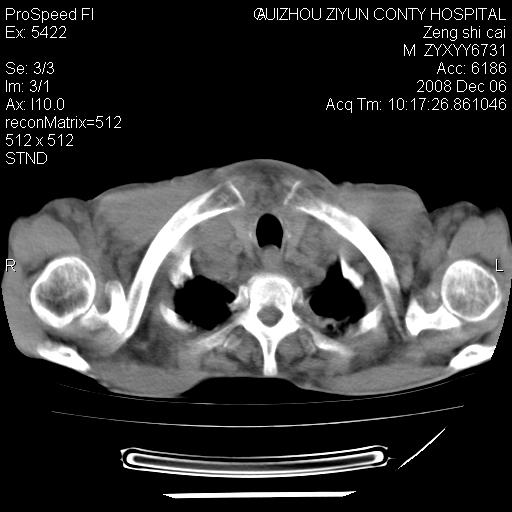

标题: CT16961:M、71岁,咳嗽半年,无血痰;胸片示右肺占位。 [打印本页]

标题: CT16961:M、71岁,咳嗽半年,无血痰;胸片示右肺占位。

右肺癌并纵隔淋巴结及胸膜转移可能性大

右肺癌并纵隔淋巴结及胸膜转移。建议气管镜

右肺纵隔型肺癌伴纵隔淋巴结及胸膜转移!

右肺纵隔型肺癌伴纵隔淋巴结转移!双侧胸水!

1)考虑右肺上叶纵隔型肺癌伴纵隔淋巴结转移。2)心包积液,双侧胸腔积液。

右肺癌并纵隔淋巴转移,腹膜后转移可能性大,两侧胸腔积液

右肺上叶纵隔型肺癌伴纵隔淋巴结转移。心包积液,双侧胸腔积液。

建议强化!主要鉴别是淋巴瘤与肺癌淋巴结转移。